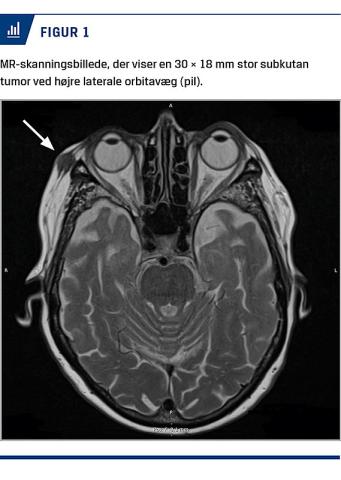

Knap et år senere blev hun genhenvist pga. tiltagende størrelse af tumoren og gennembrud til huden med sårdannelse, der var klinisk suspekt for nonmelanomhudkræft. Ultrasonisk sås et hypoekkoisk område, og der blev taget et finnålsaspirat, som var cellefattigt og inkonklusivt. Man valgte at foretage en knivbiopsi. Den histologiske diagnose var planocellulært karcinom (PCC) pga. udtalt epitelhyperplasi og uskarpt afgrænset epitel med atypi beliggende i dermis. Patienten blev med henblik på videre behandling henvist til en plastikkirurgisk afdeling, hvor man i tillæg til tidligere undersøgelser udførte en MR-skanning, som viste en 30 × 18 mm stor subkutan tumor ved højre laterale orbitavæg (Figur 1), samt en CT, som afkræftede mistanke om indvækst i knoglen. Patienten ønskede udelukkende kirurgisk behandling, og tilfældet blev derfor ikke drøftet på en multidisciplinær team-konference. Tumoren blev fjernet, og defekten lukket med direkte suturering. Det endelige histologisvar viste radikalt fjernet NXG uden tegn på det tidligere knivbiopterede PCC.